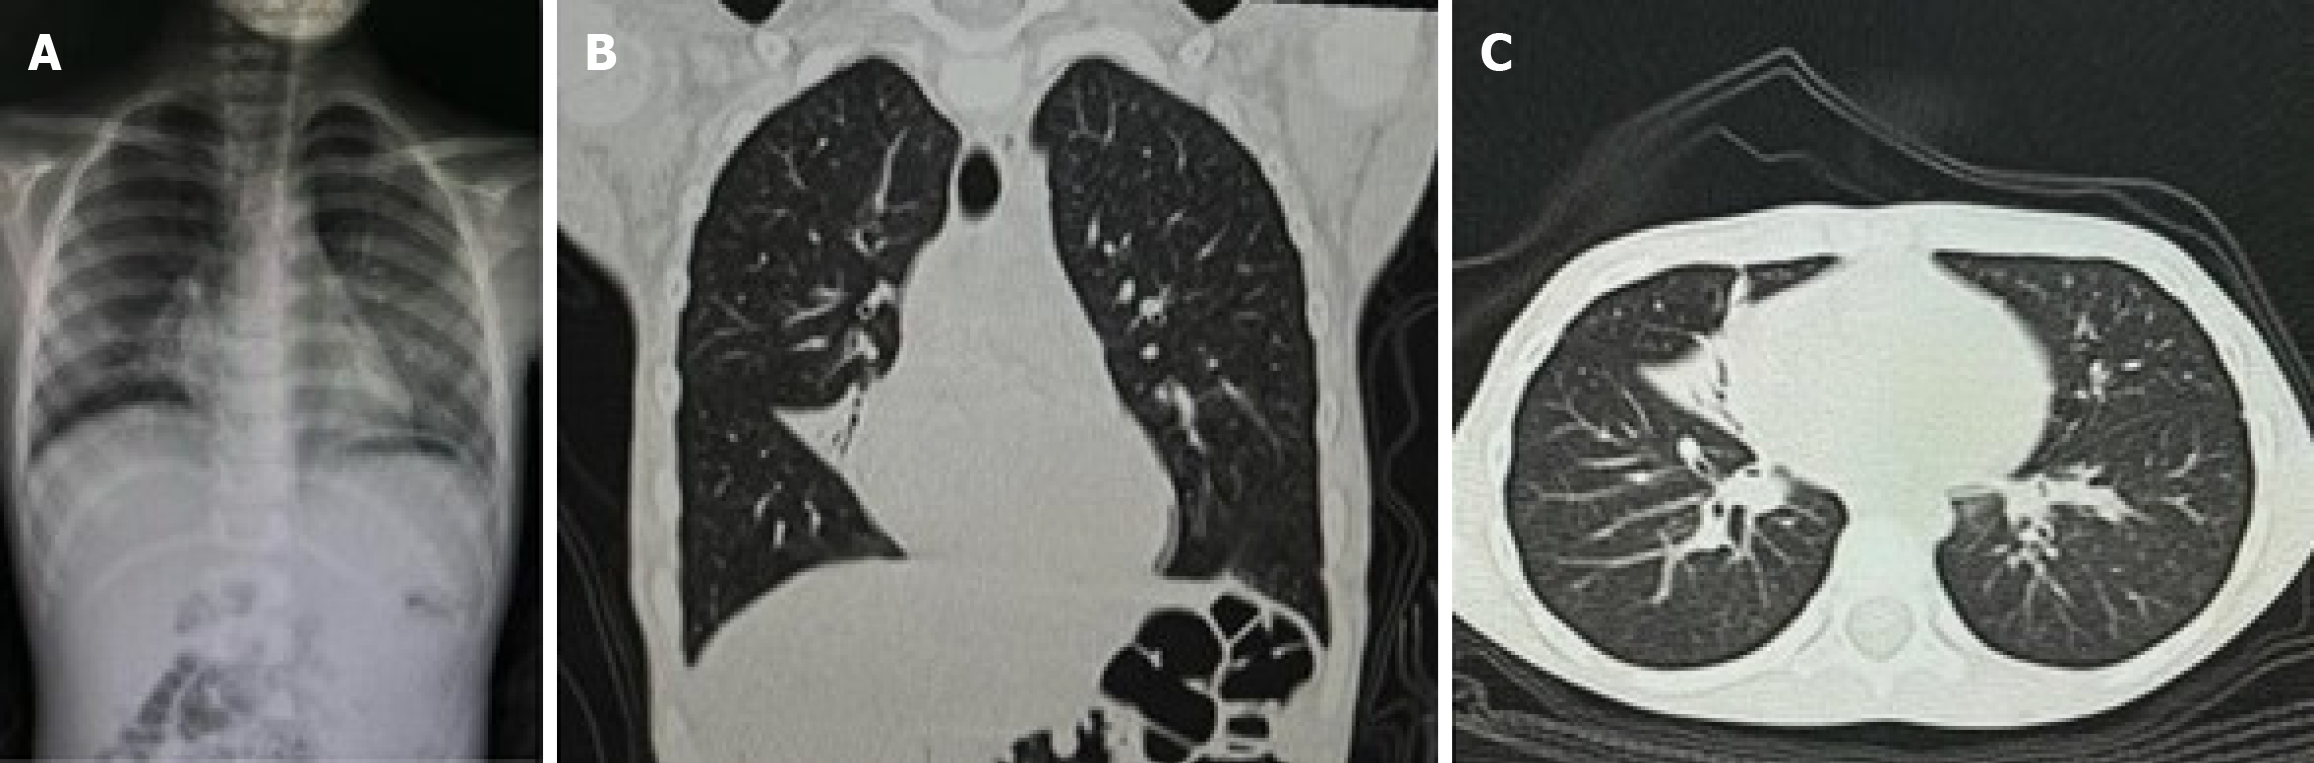

Figure 2 Chest X-ray and computed tomography.

A: Atelectatic area at the anterior right middle lobe, visible as increased opacity; B and C: Bronchiectasis in the right middle lobe with mucus plugging and segmental collapse. Shaded areas indicate disease severity.